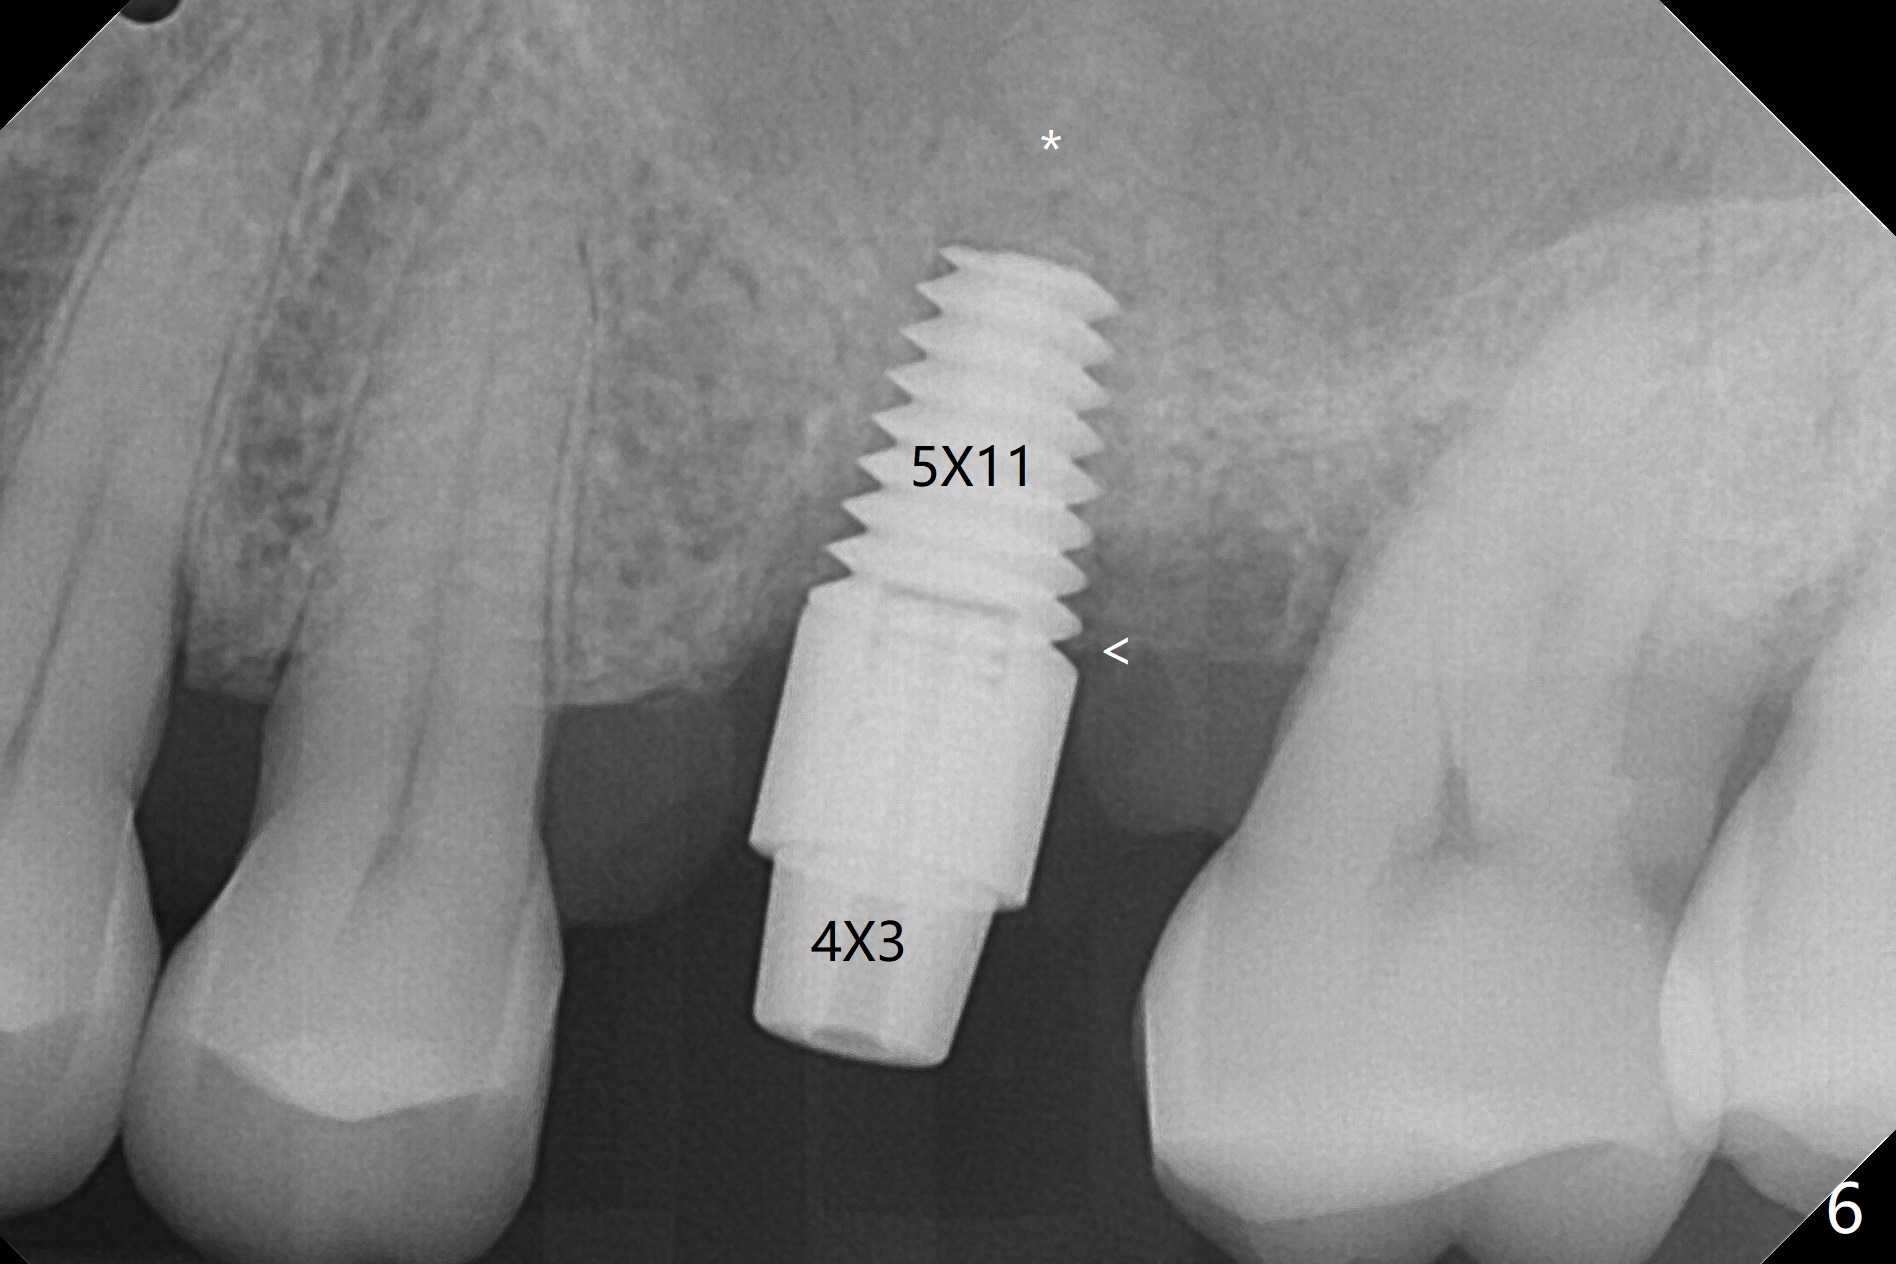

A 65-year-old man had crack tooth syndrome at #14 one month earlier (Fig.1). He shows up with crack and pain in an emergency manner (Fig.2 arrowheads). Preop CT confirms 4.5 mm bone height (Fig.3). Osteotomy will be initiated in the middle of the septum between 3 sockets (Fig.4). Depth of osteotomy is controlled with drill stoppers. After sequential osteotomy free hand, a 5x11 mm tap is used to break through the sinus floor (Fig.5) and sinus lift with Vanilla allograft. To prevent abutment screw loosening, a 5x11 mm tissue-level implant is placed; the distal thread is equicrestal (Fig.6 arrowhead). Following deeper placement of the implant (Fig.7 arrow) with a larger and longer abutment (as compared to that in Fig.6), the margin for an immediate provisional (Fig.9 white curved lines) is prepared in the coronal end of the implant (Fig.8 between arrowheads). With the tissue-level implant, the crown/implant ratio improves. Stress will be partially acting on the implant so that there is less likelihood of abutment screw loosening. The socket heals 1 month postop (Fig.10). The rough surface of the implant is exposed ~ 1 mm. With the margin modified and polished, the provisional returns to place with oral hygiene instruction. It is hoped that the gingiva will cover the exposed rough surface. The buccal rough surface remains exposed 5 months postop (Fig.11). The bone in sinus lift is mature 5 months postop (Fig.12,13). The first 1-2 implant threads are expected to be filled with mature bone in the near future (*). Since the abutment seems long enough for retention, temp bond is used for cementation (Fig.14). Water pik is being applied.